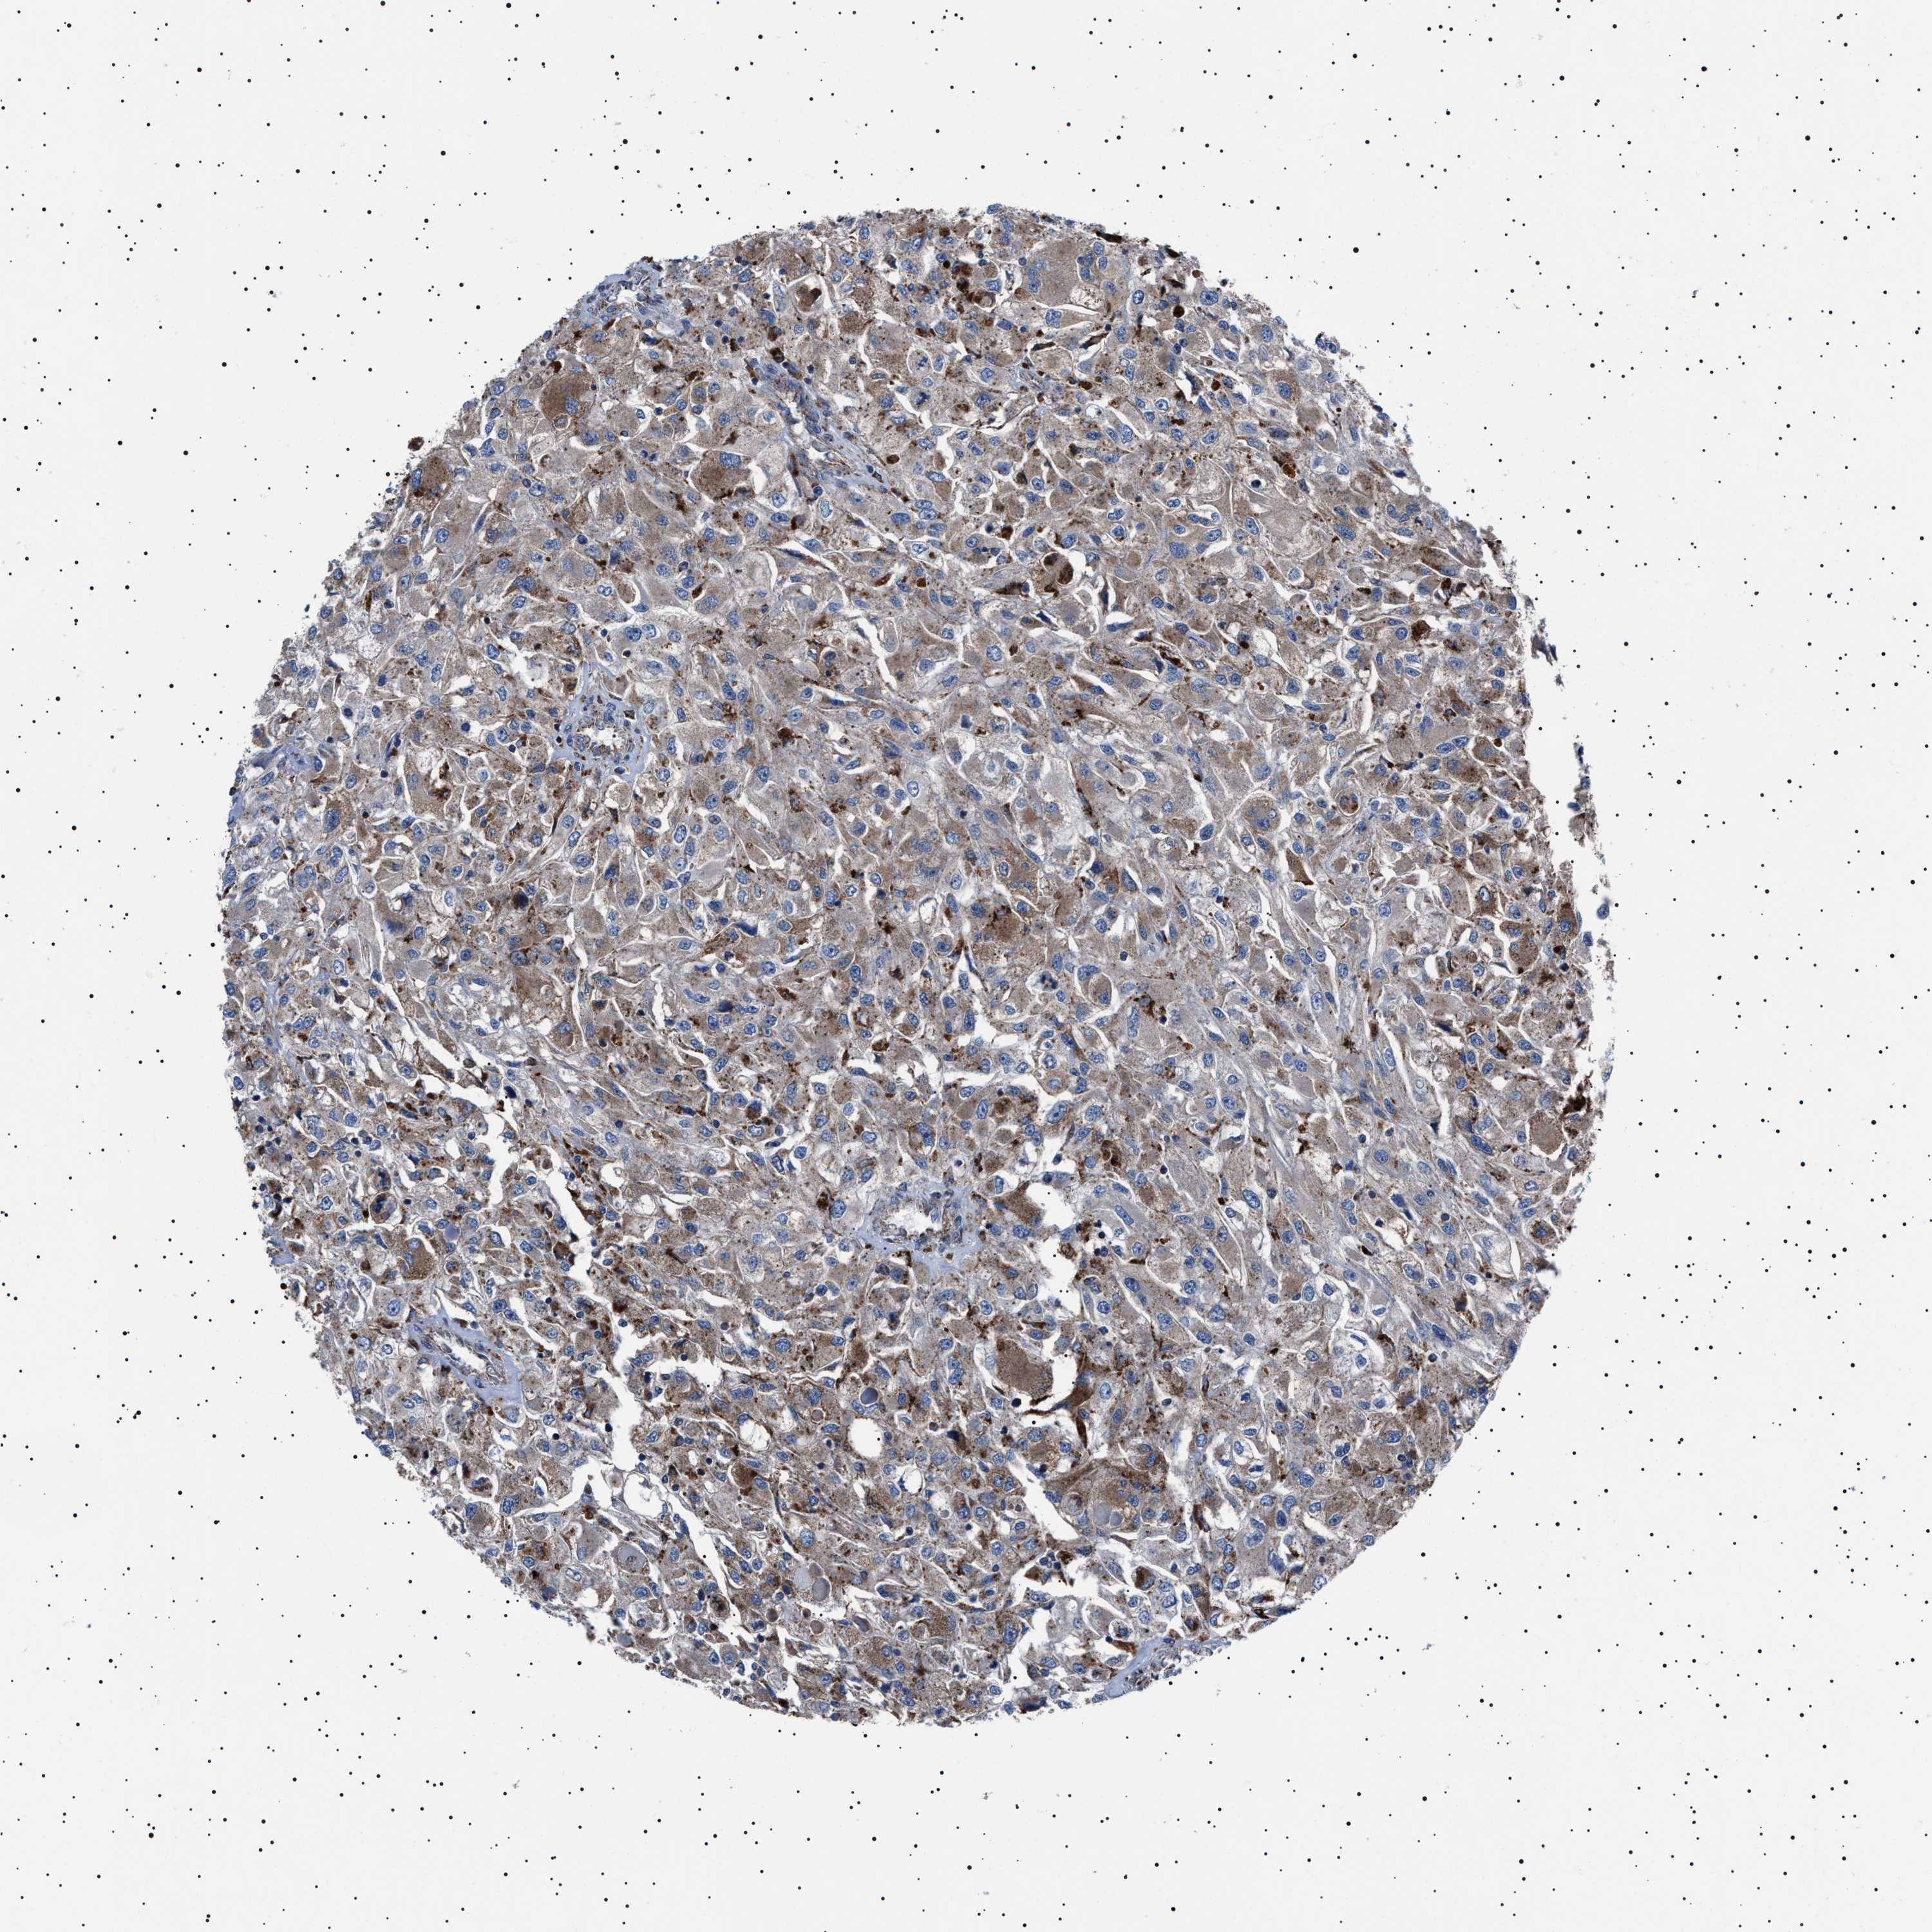

TCGA RNA samplesi

RNA-seq data is reported as average FPKM (number Fragments Per Kilobase of exon per Million reads), generated by the The Cancer Genome Atlas (TCGA) .

Normal distribution across the dataset is visualized with box plots, shown as median and 25th and 75th percentiles. Points are displayed as outliers if they are above or below 1.5 times the interquartile range. FPKM values of the individual samples are presented next to the box plot.

Average pTPM 1.3

Number of samples 521